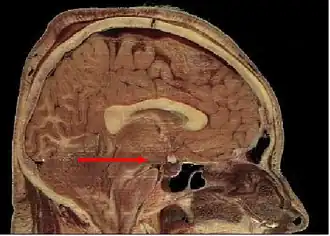

De hypothalamus[2][3] is een onderdeel van de hersenen. De hypothalamus is een onderdeel van het limbisch systeem. Het controleert het autonome zenuwstelsel en het endocriene systeem en speelt een cruciale rol bij de organisatie van gedragingen die zorgen voor de overleving van het individu en de soort: eten, vechten, vluchten, paren. Daarnaast speelt de hypothalamus ook nog een cruciale rol bij de temperatuurregeling.

De hypothalamus is een klein geheel van structuren onder (hypo) de thalamus. De hypothalamus vormt samen met de thalamus, de epithalamus en de subthalamus het diëncephalon. De hypothalamus wordt door sommigen beschouwd als onderdeel van het secundair prosencephalon.